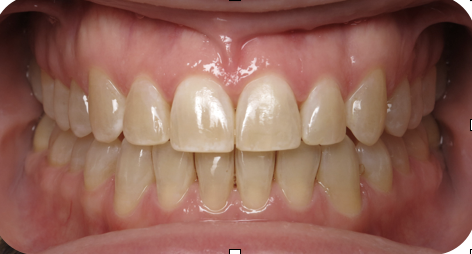

Underbite corrected with Braces

Before

After